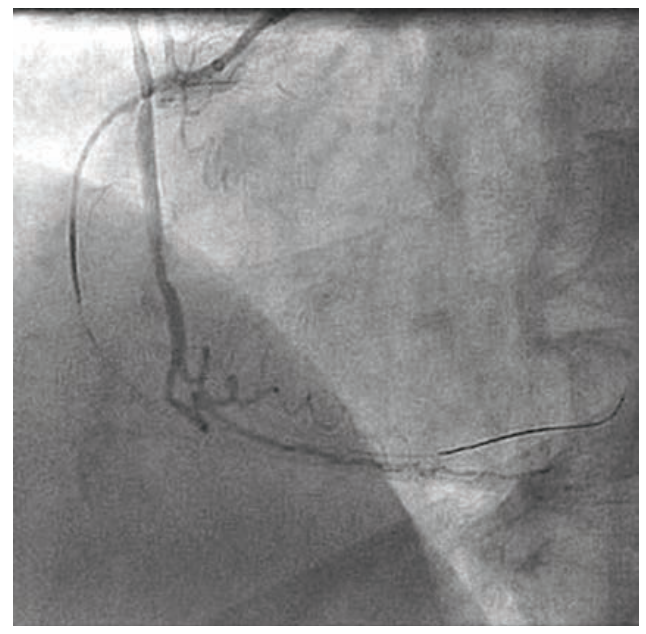

Owing to the patient’s anginal symptoms and ischemia inferiorly on the Cardiolite imaging, it was elected to open the RCA CTO. An Amplatz Left 1 6 French (Fr) guiding catheter was placed into the anterior takeoff RCA. A Turnpike Spiral microcatheter (Teleflex) with an .014-inch Minamo wire (Asahi Intecc) was initially chosen but could not traverse the stenosis, so the wire was replaced with an .014-inch Sion black wire (Asahi Intecc). This wire appeared to be extraluminal, and was removed and replaced with an .014-inch Mongo wire (Asahi) in the distal vessel, which appeared to track in the true lumen (Figure 2). A 6 Fr GuideLiner (Teleflex) was placed, but in trying to ascertain distal wire position with an injection into the GuideLiner, the vessel appeared to be dissected (Figure 3). We could see the main channel distally, and therefore took a new Minamo 300 wire and placed it into the true lumen. The Mongo wire was removed. However, the Minamo wire would not traverse into the distal vessel, so it was changed for an .014-inch Choice PT Floppy wire (Boston Scientific), which was successful in going distally. We placed a Sasuke dual lumen 145 microcatheter (Asahi Intecc), removed the Choice PT wire, and placed a Balance Middle Weight (BMW) Universal 300 wire (Abbott Vascular). A GuideLiner had been used for support and we attempted to place a Synergy 3.5 mm x 48 mm stent (Boston Scientific). However, the stent would not go forward. It was removed and found to be intact on inspection. The stent was replaced with a 3.0 mm x 30 mm Monorail Emerge balloon (Boston Scientific) for further dilatation of the RCA to 6 atmospheres (atm) for overlapping 15-second inflations. A third inflation of 12 atm for 35 seconds was performed and the balloon was removed. A 3.0 mm x 38 mm Synergy drug-eluting stent (Boston Scientific) was not able to be placed adequately distally, and was removed, inspected, and found to be intact. It appeared that the GuideLiner might be preventing some forward motion of the stent and it too was removed. There was, on angiography, a flow abnormality consistent with a small branch wire perfusion abnormality. There was no clear-cut staining. An echo showed no evidence of pericardial fluid and no tamponade physiology. It was felt that this should be addressed and so a 1.5 mm x 12 mm Takeru balloon (Terumo) was inflated to 6 atm for 20 seconds, though this did not resolve the flow abnormality. Ultimately, a 2.5 mm x 15 mm PK Papyrus covered stent (Biotronik) was delivered to the site of flow abnormality and deployed to 6 atm for 60 seconds. Angiography after balloon deflation showed no further flow into the branch (Figure 4).